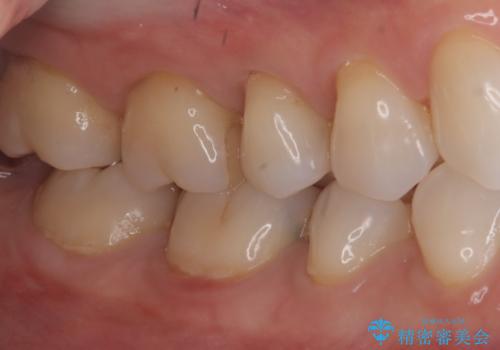

- 主訴:右下の奥歯がたまに冷たい物や甘いものでしみる

右下6番目の歯に大きめのう蝕を認め、形態の再現性を考えインレーでの治療となりました。

右下6の近心にう蝕が認められう蝕の範囲が大きかったため、歯冠形態の再現性の高いインレーでの修復とし、材質は審美性、清掃性に優れたセラミックを選択しました。